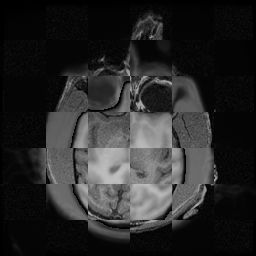

For each of the 10 subjects, we show checkerboard slices in each direction (1) before registration, first row; (2) after rigid->scaleversor->affine registration, second row; and (3) after BSpline registration, third row.

Note the unsuccessful BSpline registration result for Issac.

Issac

Issac is a good example of BSpline registration failure.

Ron noted, the reason might be that Issac had his mouth open, unlike most of the subjects registered successfully.